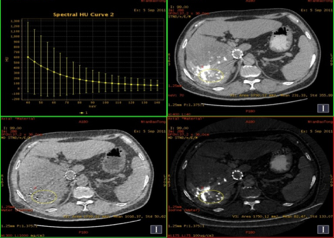

男性,56岁,肝癌栓塞术后复查。

能谱分析

平扫:碘9.03,水1018.90

动脉期:碘8.56,水1016.22

静脉期:碘8.25,水1016.37

缩小ROI后放在病灶碘油未沉积区比较如下:

平扫:碘2.05,水1001.88

动脉期:碘1.66,水1009.80

结论:此例平扫、增强多期碘基物质定量无显著差异。栓塞治疗效果较好。

临床优势:肝癌栓塞后,因碘油和术后炎性反应的影响,短期内难以评估手术效果。通过能谱成像GSI分析,比较增强后碘含量与平扫时碘含量(有时可用水含量)的变化及变化趋势,来判断肝癌病灶是否还有强化,评估栓塞治疗的疗效和预后,并可指导临床进一步治疗。